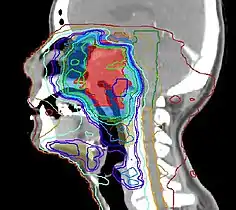

Radiation Oncology is a concise review of the radiation oncology field including a review of pertinent literature. Designed as a primer for students of radiation oncology, but may also be useful for those in practice to review areas of interest.